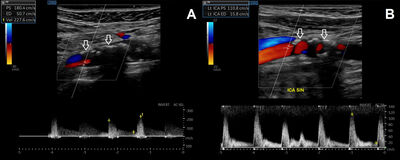

Vegna nýrnabilunar fór hún í ómun af hálsæðum sem sýndi töluverðar þrengingar í báðum fremri hálsslagæðum; nær lokun í innri hálsslagæð hægra megin og um 45% þrengingu í sömu æð vinstra megin (mynd 2). Taugaskoðun var eðlileg. Hún var sett á háskammta statínmeðferð og var fyrir á hjartamagnýli. Einnig var dregið úr blóðþrýstingsmeðferð sem hafði góð en ekki nægjanleg áhrif.

Mynd 2. Ómun með blóðflæðirannsókn af hálsslagæðum. Kalkanir (örvar) sjást í veggnum á hægri innri hálsslagæð (mynd A) og vinstri innri hálsslagæð (mynd B). Erfitt er að fá gott flæðissnið frá hægri innri hálsslagæð, en hámarkshraði blóðflæðis er metinn á að minnsta kosti 227 cm/s og því virðist um rúmlega 90% þrengingu eða jafnvel nær lokun á æðinni að ræða. Vinstra megin er blóðflæðihraðinn í innri hálsslagæð um 111 cm/s í útfallsfasa og um 16 cm/s í aðfallsfasa, sem svarar til minna en 50% þrengingar.